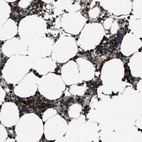

Immunohistochemical staining of human bone marrow shows distinct cytoplasmic positivity in hematopoietic cells.